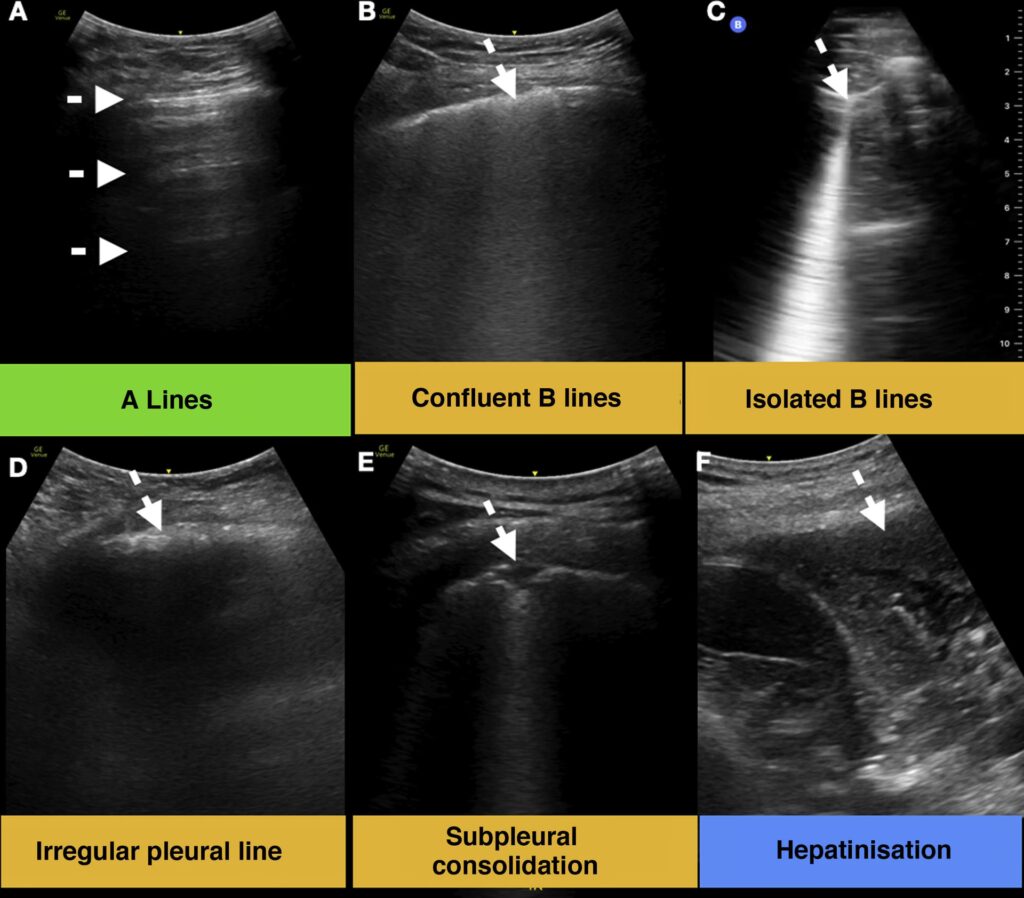

A-linjer: Tegnet på en Luftfyldt Lunge

A-linjer er det mest almindelige fund i en normal, rask lunge. De fremstår som lyse, vandrette linjer, der løber parallelt med lungehinden. Disse linjer er i bund og grund ekkoer, der reflekteres frem og tilbage mellem ultralydsproben og lungehinden. Deres tilstedeværelse indikerer, at der er luft i lungevævet under hinden. Selvom A-linjer er normale, kan de være særligt fremtrædende ved tilstande, hvor der er unormalt meget luft i lungerne, såsom ved astma eller Kronisk Obstruktiv Lungesygdom (KOL).

B-linjer: Når Væske eller Fortykkelse Tager Over

B-linjer er stjernen i showet, når det kommer til at diagnosticere mange lungesygdomme. I modsætning til de vandrette A-linjer er B-linjer lodrette, laser-lignende artefakter. De starter ved lungehinden og strækker sig hele vejen ned til bunden af ultralydsskærmen. En afgørende egenskab ved B-linjer er, at de bevæger sig synkront med lungens glidende bevægelse under vejrtrækning og udvisker eventuelle A-linjer i deres vej.

Når en læge ser mere end tre B-linjer inden for et enkelt scanningsområde, kaldes det et 'interstitielt syndrom'. Dette er et stærkt tegn på, at der er en øget tæthed i lungevævet – typisk forårsaget af væske eller fortykkelse af vævet mellem lungeblærerne (interstitiet). Derfor er B-linjer et centralt fund ved tilstande som:

C-linjer og Hepatisation: Tegn på Lungekonsolidering

C-linjer er et mere specifikt fund, der ofte ses i forbindelse med lungebetændelse. De indikerer en fortykkelse af selve lungehinden. I mere fremskredne tilfælde af lungebetændelse kan man se et fænomen kaldet 'hepatisation'. Her har betændelsen gjort lungevævet så tæt og solidt, at det på ultralydsbilledet ligner levervæv. Dette er et klart tegn på, at lungeblærerne i området er fyldt med inflammatorisk materiale i stedet for luft.